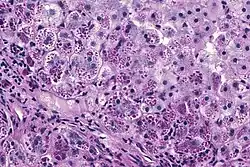

Photomicrograph of a liver biopsy from a patient with alpha-1 antitrypsin deficiency. The PAS with diastase stain shows the diastase-resistant pink globules that are characteristic of this disease.

With A1AT deficiency, the pathogenesis of the lung disease is different from that of the liver disease, which is caused by the accumulation of abnormal A1AT proteins in the liver, resulting in liver damage.[9] As such, lung disease and liver disease of A1AT deficiency appear unrelated, and the presence of one does not appear to predict the presence of the other.[9] Between 10% and 15% of people with the PiZZ genotype will develop liver fibrosis or liver cirrhosis, because the A1AT is not secreted properly and therefore accumulates in the liver.[18] The mutant Z form of A1AT protein undergoes inefficient protein folding (a physical process where a protein chain achieves its final conformation). 85 percent of the mutant Z form are unable to be secreted and remain in the hepatocyte.[9] Nearly all liver disease caused by A1AT is due to the PiZZ genotype, although other genotypes involving different combinations of mutated alleles (compound heterozygotes) may also result in liver disease.[9] A liver biopsy in such cases will reveal PAS-positive, diastase-resistant inclusions within hepatocytes.[9] Unlike glycogen and other mucins which are diastase sensitive (i.e., diastase treatment disables PAS staining), A1AT deficient hepatocytes will stain with PAS even after diastase treatment - a state thus referred to as "diastase resistant". The accumulation of these inclusions or globules is the main cause of liver injury in A1AT deficiency. However, not all individuals with PiZZ genotype develop liver disease (incomplete penetrance), despite the presence of accumulated mutated protein in the liver.[9] Therefore, additional factors (environmental, genetic, etc.) likely influence whether liver disease develops.[9]